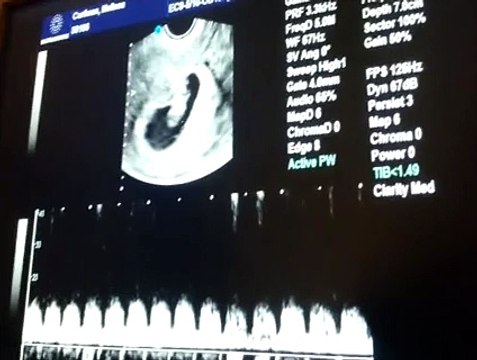

33 Haftalık Gebelik Bebek Ultrason Görüntüsü

Hafta hafta gebelik dönemi 33 haftalık bebek ultrason görüntüsü. Gebelikte 33. hafta daha çok bilgi için gebelikveannelik.com/33-hafta-gebelik sayfamızı ziyaret edebilirsiniz.